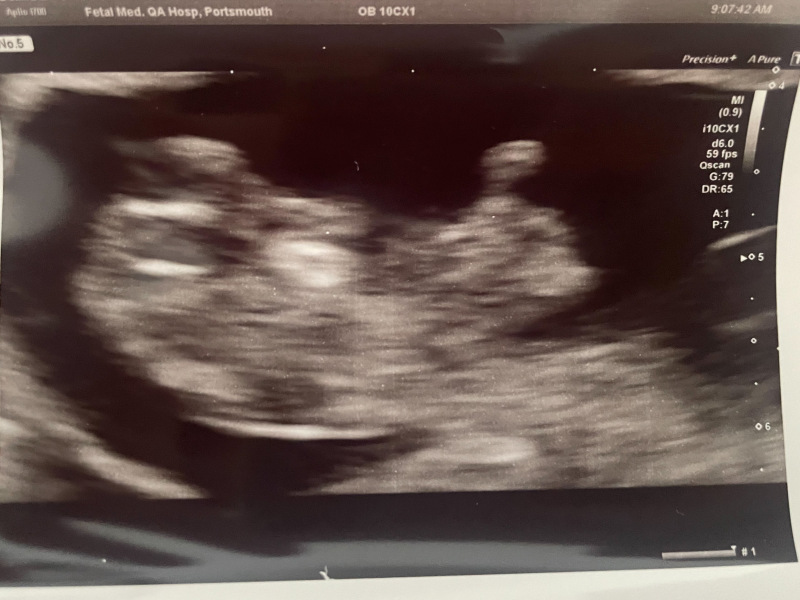

Morning ladies, pleased to report all well with my scan this morning! Measuring 9+3 which I am today and heartbeat a strong 170. Little limb buds waving around which was lovely to see. We're over the moon ❤️

@CosmicLove ahhh so so happy for you!! What an amazing scan photo 😍😍